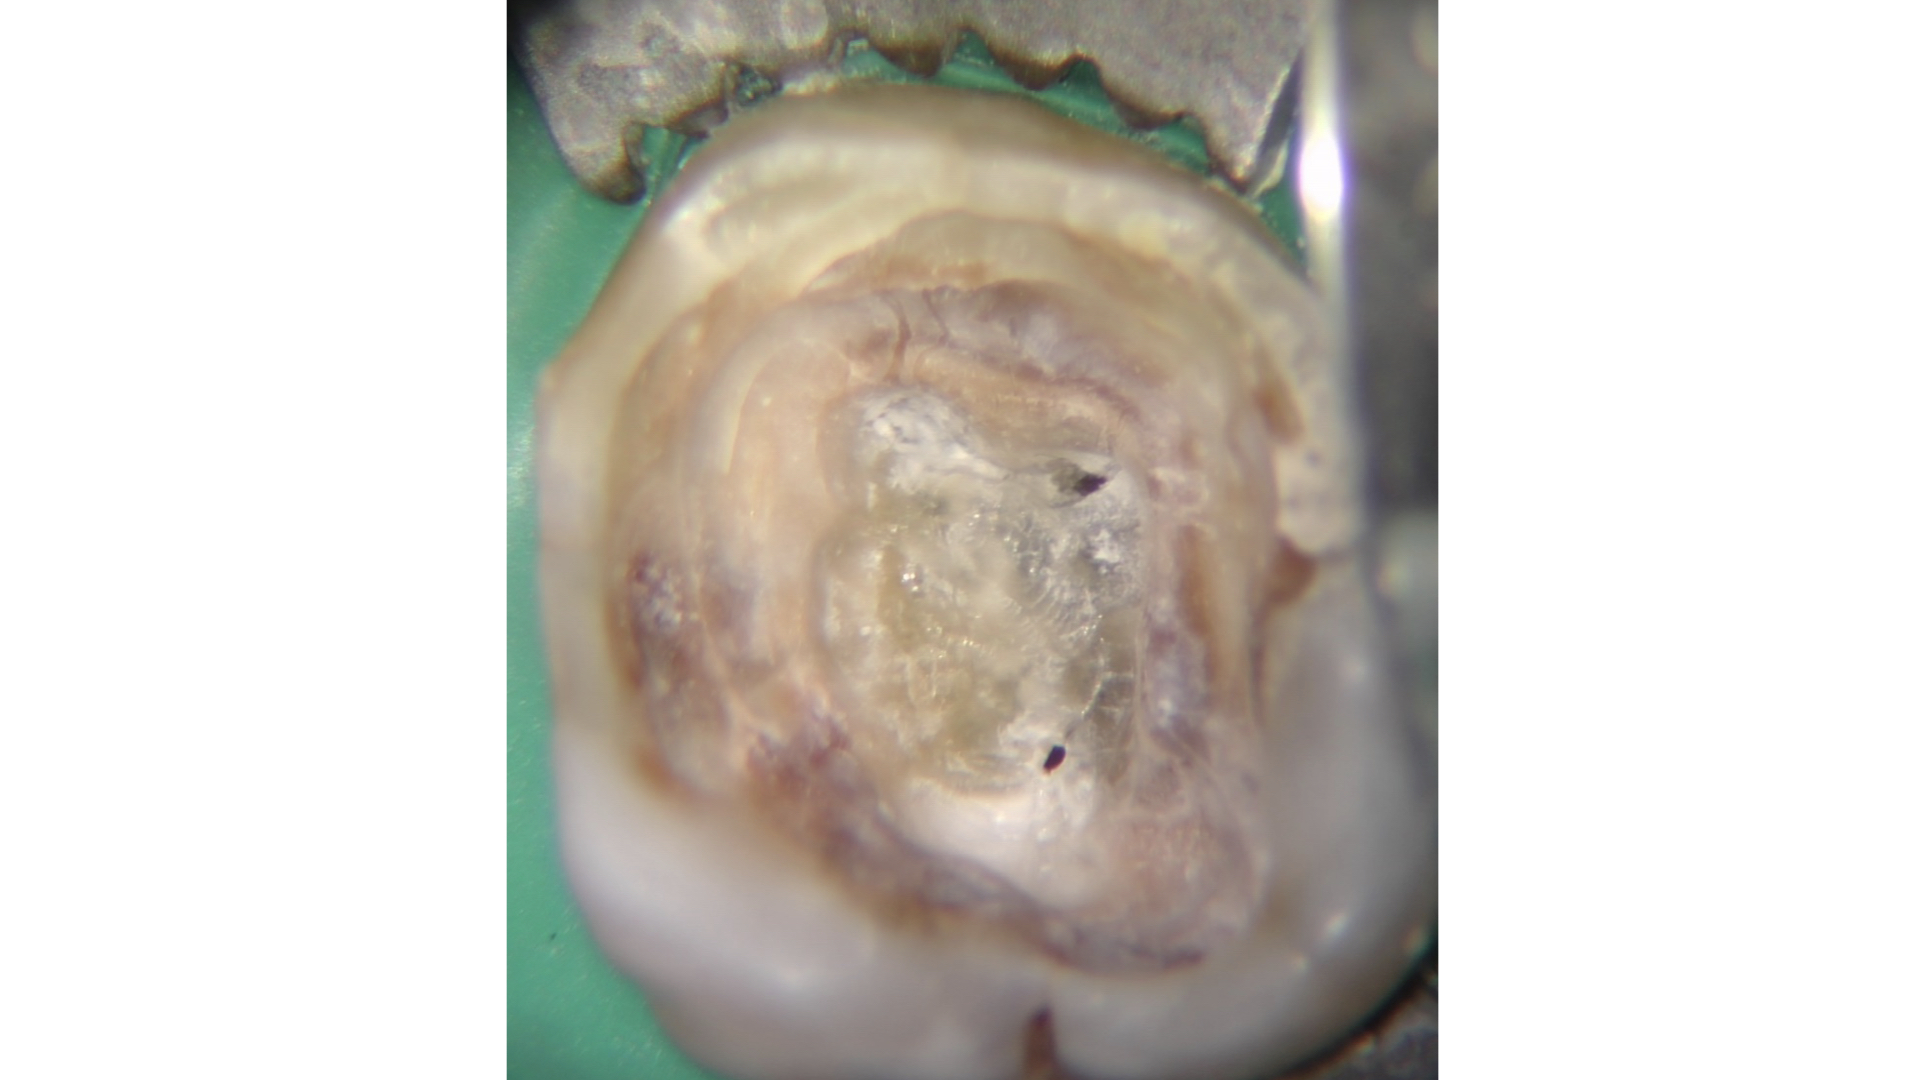

Qualora invece l’ostruzione si estendesse più in profondità, la regola della polvere dentinale può servire come guida per il clinico. Questa regola trae il suo fondamento da una delle leggi di Krasner e Rankow7, quella del cambio di colore.

Il sistema canalare è sempre contenuto in un’area più scura rispetto alle pareti canalari e quindi l’azione di avanzamento è guidata proprio da questo assunto cromatico.

Consumando lentamente dentina in direzione apicale (a secco, a basso numero di giri, raffreddando con la siringa ad aria) pochissimi decimi di millimetro per volta si manterrà la corretta centratura all’interno della radice e si potrà visualizzare ad un certo punto una traccia bianca: non si tratta altro che di polvere dentinale prodotta dall’azione dello strumento rotante che si deposita in maggiore quantità proprio in corrispondenza della traccia dell’orifizio.

Lo strumento ideale per avanzare alla ricerca del canale è ancora una volta Endotracer. Il gambo lungo (disponibile anche nella versione 34 mm, oltre che 31 mm) consente di poter avere sempre controllo visivo sull’avanzamento.

I diametri utilizzati vengono scelti in base alla profondità: via via che si procede apicalmente è necessario ridurre il diametro e anche la velocità di utilizzo, oltre che fare pause di controllo sempre più frequenti.

Questa azione di consumo selettivo della dentina può rendere visualizzabile in tempi molto brevi la traccia “bianca” di polvere depositata sull’orifizio; qualora invece i primi passaggi non avessero reso possibile la localizzazione è opportuno alternare irrigazione con ipoclorito di sodio e asciugatura per poi ripartire con un nuovo ciclo di escavazione (Figure 27-33).